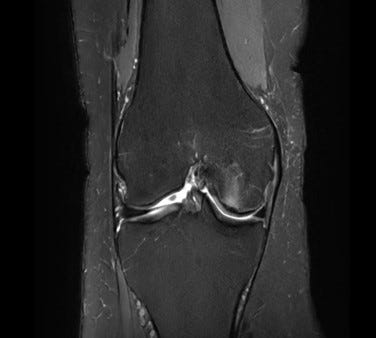

An MRI finally explained why: a subchondral insufficiency fracture of my femoral condyle. (The white shadowy image seen receding from the cartilage)

A subchondral insufficiency fracture (SIF) occurs just beneath the cartilage surface, at the load-bearing platform of the joint. These fractures aren’t caused by a dramatic event, they happen when normal forces exceed weakened bone architecture.